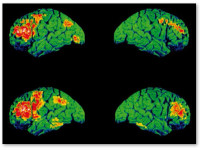

Исследование группы ученых из Университета Манчестера проливает новый свет на то, как употребление марихуаны влияет на шизофрению.   Согласно отчету, опубликованному в журнале Schizophrenia Bulletin 9 июля, ученые наблюдали за ...